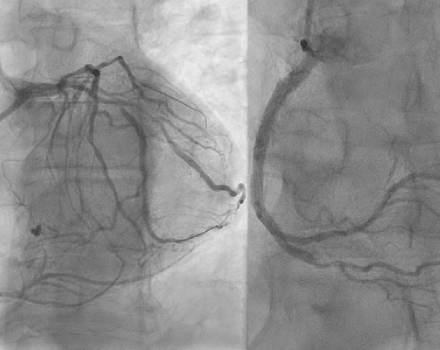

Coronary Artery Disease

Coronary artery disease is defined as the buildup of atherosclerotic plaque (atherosclerosis) within the walls of the coronary arteries—vessels that supply the heart muscle (myocardium) with the oxygen-rich blood necessary for its continuous and proper function.

Στεφανιαία Νόσος

Ως στεφανιαία νόσο ορίζουμε την εναπόθεση αθηρωματικής πλάκας (αθηροσκλήρυνση) στο εσωτερικό του τοιχώματος των στεφανιαίων αρτηριών, των αγγείων, που τροφοδοτούν το μυ της καρδιάς (μυοκάρδιο) με την απαραίτητη, για τη συνεχή και φυσιολογική λειτουργία του, ποσότητα αίματος και οξυγόνου.